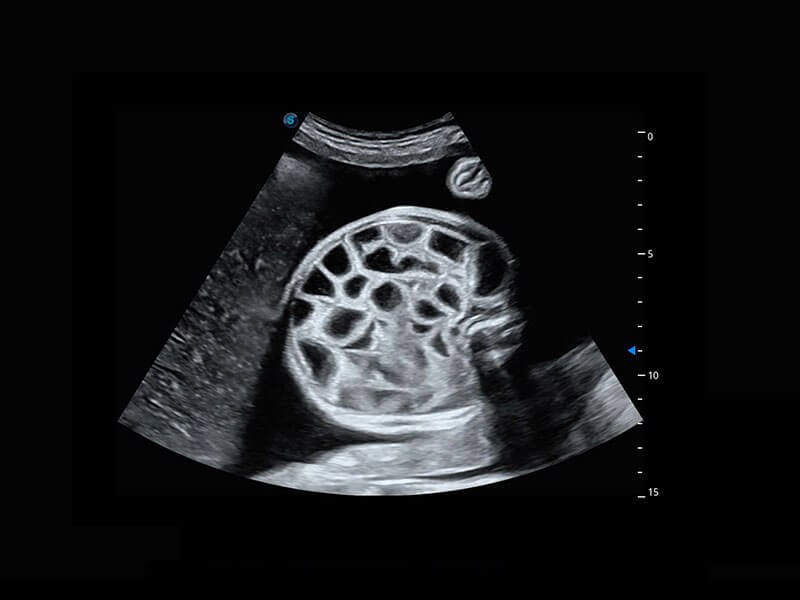

胎心筛查

P60搭载一系列胎儿心脏成像技术,实现精细的胎儿心脏评估。

• 胎心容积成像